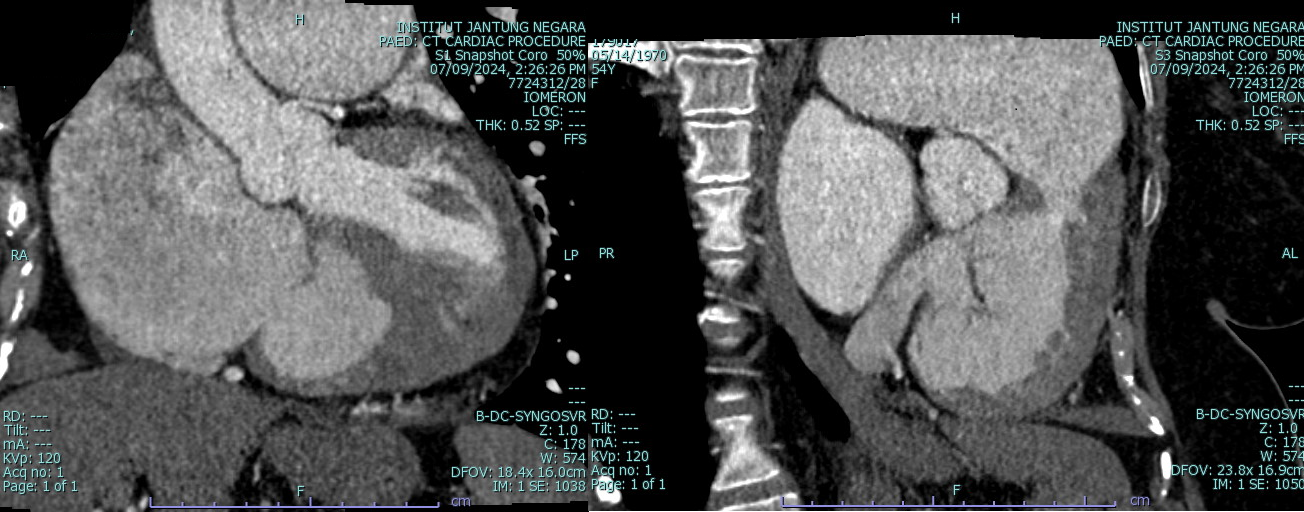

CT scan (CTPA and CT coronary) : Resolved pulmonary artery thrombosis, Normal epicardial coronary arteries. ASD measures 3.2 x 2.9 cm

CT scan (CTPA and CT coronary) : Resolved pulmonary artery thrombosis, Normal epicardial coronary arteries.

This case highlights our patient with longstanding secundum ASD and pulmonary arterial hypertension who developed dynamic left main coronary compression by a dilated pulmonary artery, confirmed on IVUS (MLA 12.8¡æ6.7 mm©÷, minimal plaque). Cardiac MRI showed Qp:Qs 1.86 and right-sided dilatation; right-heart catheterization revealed elevated but partially reversible PVR (4.9¡æ3.8 WU with iNO). A multidisciplinary, safety-first ¡°treat-and-reassess¡± strategy (targeted PAH therapy with planned fenestrated ASD closure if PVR improves) avoided premature high-risk interventions and provides a practical framework for similar complex ACHD patients.